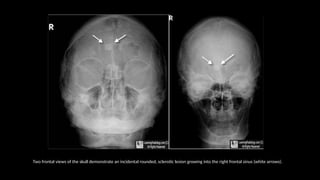

Occipitofrontal view

 This projection is used to demonstrate the frontal and

ethmoidal sinuses.

 It is also known as the Caldwell’s view.

 The patient is seated upright in front of the receptor and their

forehead and nose are placed against it.

 The beam is centred at around 15 to exit at the nasion.

⁰

• collimation

• lateral to the skin margins

• superior and inferior to the borders of the sinus cavities

Two frontal views of the skull demonstrate an incidental rounded, sclerotic lesion growing into the right frontal sinus (white arrows).

z Occipitofrontal view  Thisprojection is used to demonstrate the frontal and ethmoidal sinuses.  It is also known as the Caldwell’s view.  The patient is seated upright in front of the receptor and their forehead and nose are placed against it.  The beam is centred at around 15 to exit at the nasion. ⁰ • collimation • lateral to the skin margins • superior and inferior to the borders of the sinus cavities

Two frontal viewsof the skull demonstrate an incidental rounded, sclerotic lesion growing into the right frontal sinus (white arrows).